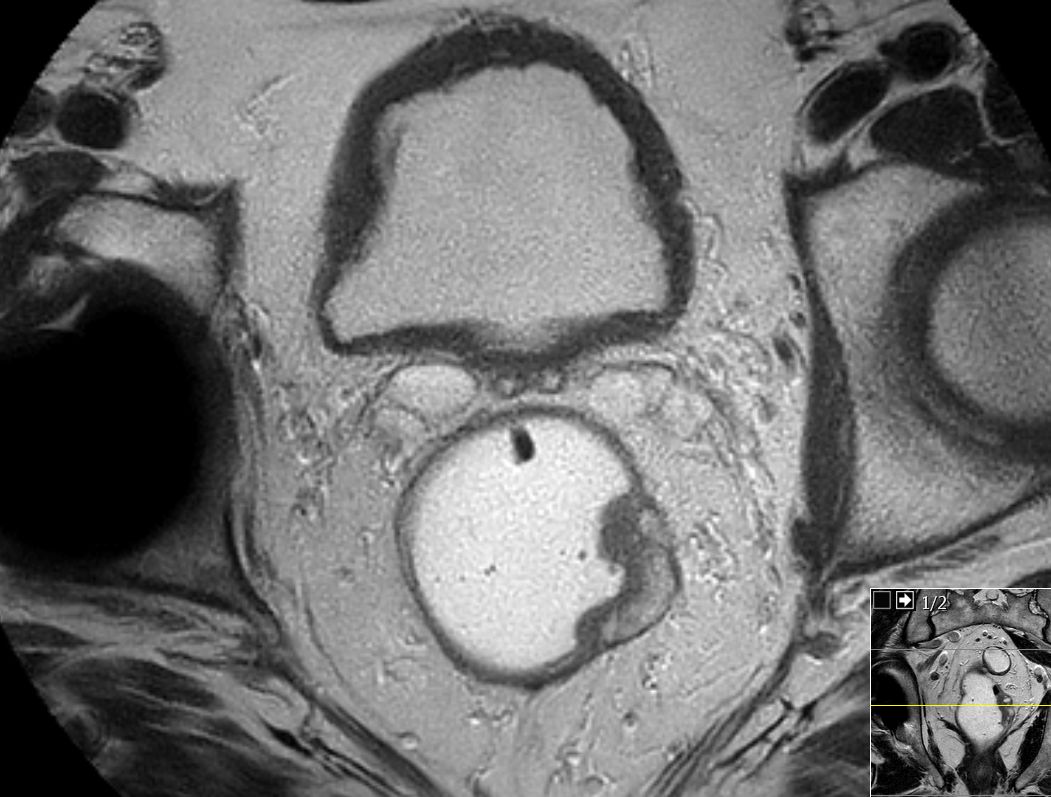

| MRT: T2 | 69-jähriger Mann mit mäßig differenziertem

Adenokarzinom bei 15 cm.![]() |

![]() |

![]() | |